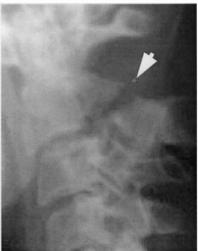

Lateral View

- All C- vertebrae & upper T1

- Prevertebral soft tissue width

- Four parallel curves

- Front of vertebral bodies

- Back of vertebral bodies

- Posterior borders of lateral masses

- Bases of spinous processes